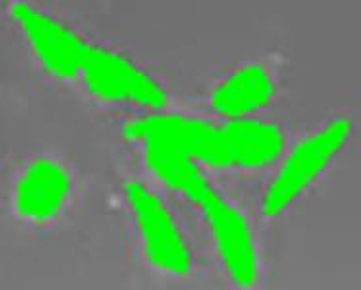

Mitotic cells are defined as those cells before, during and after mitosis. During mitosis, obvious morphological changes usually occur, which make them look different from normal cells, i.e., cells in non-mitosis status. In Fig. 2, from left to right, morphological changes of a cell before, during and after mitosis.

Figure 2: Morphological changes in mitosis.